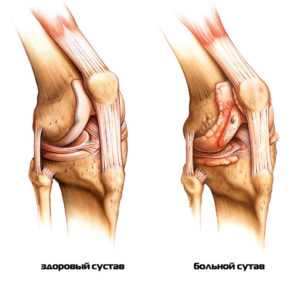

Π Π΅Π°ΠΊΡΠΈΠ²Π½ΡΠ΅ Π°ΡΡΡΠΈΡΡ